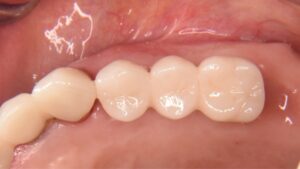

たとえば奥歯を1本失うと、前歯で噛む割合が増え、被せ物や残っている歯に負担が移ります。奥歯は咬合支持といって、噛む力を後方で支える役割を持ちます。これが減ると、見た目の問題より先に、食事のしづらさや顎の疲れとして表れることがあります。補綴の視点では、インプラントは「空いた場所を埋める治療」ではなく、「どこに力を戻すかを設計する治療」です。だから、名古屋で「名古屋 インプラント」を検討する方にこそ、CT画像、模型、咬合記録を使った診断の質を見ていただきたいと考えています。